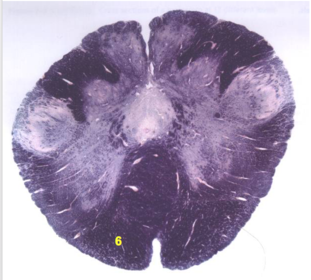

| Longitudinal pontine fibers (corticospinal tract) | |

| Transverse pontine fibers (dark fibers) | |

| Pontine nuclei (pale) | |

| Medial lemniscus | |

| ALS | |

| Trapezoid body | |

| Ventral trigeminothalamic tract | |

| Superior olive | |

| Central tegmental tract | |

| Facial nerve root fibers - descending | |

| Facial motor nucleus | |

| Interposed nuclei | |

| Medial longitudinal fasciculus | |

| Facial nerve root - internal genu | |

| Abducens nucleus | |

| Lateral vestibular nucleus | |

| Superior vestibular nucleus | |

| Inferior cerebellar peduncle | |

| Superior cerebellar peduncle | |

| Dentate nucleus | |

| Fastigial nucleus | |

| Anterior spinocerebellar tract | |

| Spinal nucleus of V | |

| Spinal tract of V | |

| Middle cerebellar peduncle | |

| Principle nucleus of V | |

| Mesencephalic V tract | |

| Trigeminal root fibers | |

| Motor nucleus of V | |